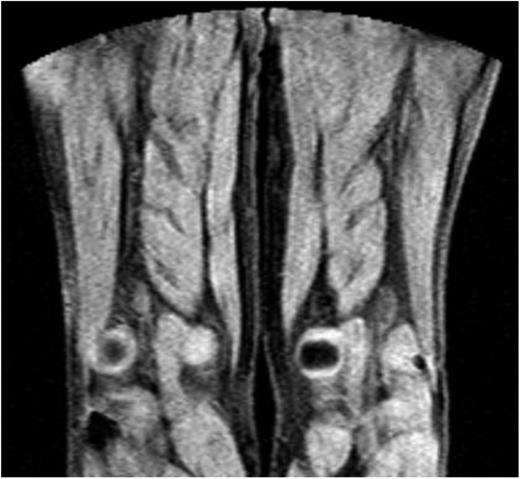

MRDTI was normal in all 42 patients of group 2, who had chronic thrombosis on CUS and no symptoms of acute recurrent DVT. Figure 2 depicts the normal MRDTI signal in a patient from study group 2 with asymptomatic residual thrombosis.

MDRTI image of a patient with ultrasonography-proven residual DVT but no acute recurrent thrombosis in the popliteal vein of the right leg. The scan did not indicate an abnormal MRDTI signal.

Our study did not establish the definite role of MRDTI in the most optimal diagnostic algorithm for suspected acute recurrent ipsilateral DVT. The group 1 patients do not represent the full spectrum of patients with an acute recurrent DVT; those being given anticoagulant treatment with longer symptom duration or those with inconclusive CUS results were not included. Second, the strength of a D-dimer test in combination with a clinical decision score to identify patients with a very low pretest risk in this specific patient category who can be managed without imaging is yet to be established. Although in 1 study, normal D-dimer levels were shown to rule out the presence of acute symptomatic recurrent DVT, the broad confidence interval and high point estimate of 6.0% (95% CI, 2.6% to 11%) for recurrent disease despite a normal D-dimer level in that study argue against a role for D-dimer as a stand-alone test to rule out recurrent DVT.14 MRDTI has the potential to be used as a first-line imaging test, or as a second-line test for those patients in whom ultrasonography does not provide a conclusive test result. In addition to the high diagnostic accuracy, the fast, noninvasive, patient-friendly nature of MRDTI is a strong argument for the former scenario. Conversely, acute accessibility in the emergency department setting may be limited in some hospitals. Importantly, in the latter scenario of MRDTI being the second test after inconclusive CUS, standardized reference ultrasonography recordings should still be performed in all patients after treatment cessation. Strengths of the study include the application of an efficient design. One group of patients with symptomatic ipsilateral recurrent DVT, based on strict CUS criteria as well as a positive D-dimer test, formed the basis for an accurate sensitivity estimation, whereas patients with a residual thrombosis and negative D-dimer test provided a precise specificity estimation. By this design, this is the first study that was able to address the accuracy of MRDTI in a specific series of patients with acute ipsilateral recurrent DVT. This design had also been successfully applied previously for the evaluation of a new scintigraphy in the diagnostic work-up of suspected recurrent ipsilateral DVT.16 Furthermore, exclusion criteria were designed to exclude only those patients who could not undergo MRDTI and those in whom the group 1 or 2 status could not be established with 100% certainty. In addition to evaluating the diagnostic accuracy of MRDTI, we studied its feasibility in daily clinical practice. Not only did we demonstrate a high reproducibility of the MRDTI results, MRDTI images in all participating hospitals were of good quality, suggesting that MRDTI could be broadly applicable on different MRI machines. The most important limitation of the study is that, by design, the subgroup of patients for which it is hoped MRDTI would be most helpful (ie, those with suspected recurrent DVT and inconclusive CUS) was not part of this study. A further limitation was that only patients with normal D-dimer levels were selected in the control group without recurrent DVT. Although this indeed is a strong argument for the absence of acute DVT, higher D-dimer levels are common in asymptomatic patients after completion of a 6-month treatment period for acute venous thromboembolism (VTE) and are associated with more extensive residual thrombosis as well as a higher recurrence risk.17,18 Hence, although it is unlikely, we cannot rule out the possibility that the excellent specificity observed in our study might be an overestimation resulting from the selection of relatively nonsevere cases of residual thrombosis. Finally, the MRDTI images were read by readers who were already experienced MRDTI readers, possibly resulting in an overestimation of the reproducibility of the readings and generalizability to other settings. Even so, the images are relatively easy to read (Figures 1 and 2), and specific training of radiologists, in our experience, does not prove to be a major effort.